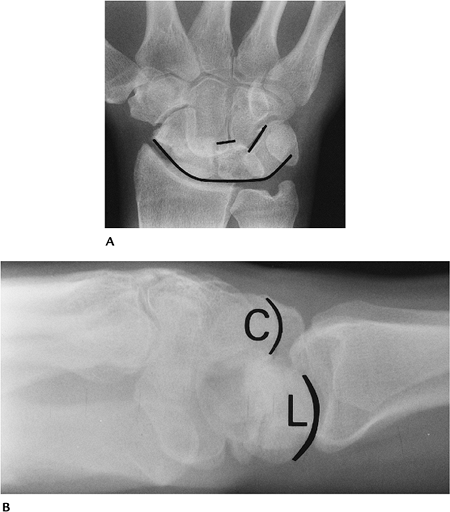

Fractures/Dislocations: Carpal and Carpometacarpal Dislocations

-

Dislocations of the carpus are most often associated with perilunate injury.

The transscaphoid perilunate dislocation

is most common. The proximal scaphoid maintains its lunate

relationship, and the distal scaphoid and remainder of the carpal bones

displace dorsally. -

Carpometacarpal dislocations are most often associated with distal carpal or metacarpal base fractures.

Mechanism of injury: fall on the outstretched hand.

Imaging may be accomplished with PA and

lateral radiographs. CT is best for subtle cases, evaluation of

osteochondral fractures, treatment planning, and postreduction

evaluation. -

Treatment: closed reduction if alignment can be restored; otherwise internal fixation.

Complications: arthrosis, AVN, instability.

![]() |

FIGURE 9-20 Transscaphoid perilunate dislocation seen on PA (A) and lateral (B) radiographs. The lunate and proximal scaphoid are in nearly normal position on the PA view (A). The second carpal row is irregularly aligned (lines). The displacement of the capitate (C) compared with the lunate (L) is obvious on the lateral view.